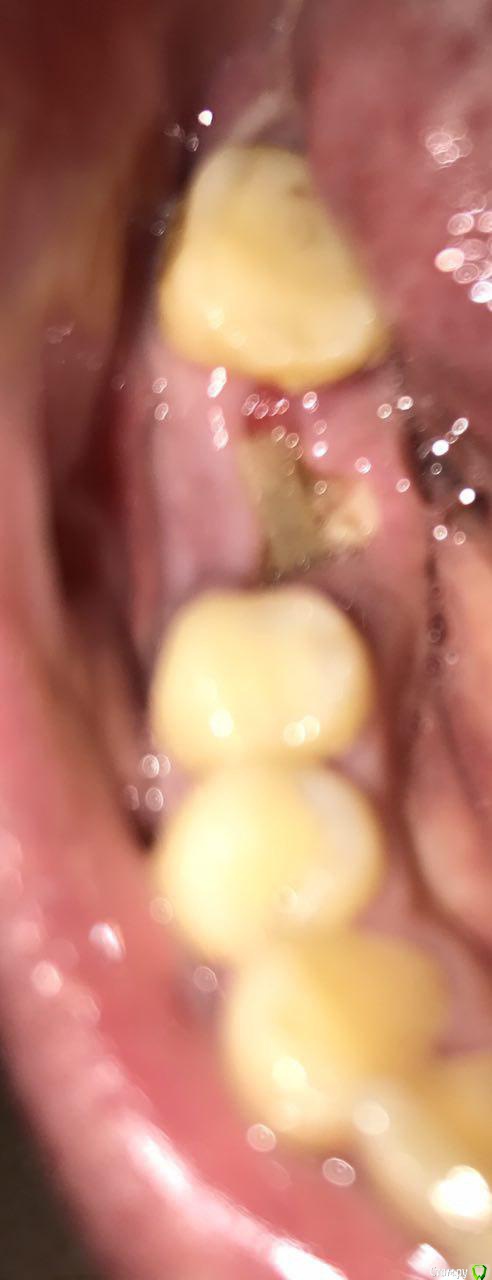

annag Опубликовано 10 сентября, 2017 Поделиться Опубликовано 10 сентября, 2017 Всем добрый день!В субботу 2 сентября удалил нижнюю шестерку, так как была большая киста, планирую поставить имплант.Удаление было сложным, зуб сам по себе большой, пришлось распиливать пополам и удалять частями. Удалили минут 30. В итоге по словам хирурга прошло всё нормально, один корень был с расширением на конце, поэтому так сложно. Положили в лунку какую-то губку, лекарств не назначили, кроме обезболивающих.Дальше с первого дня лунка начала болеть и так болела всю неделю. А мне улетать в понедельник 11.09, поэтому начал напрягаться. Боли слабее не становились, по ночам особенно. Спасался кетановом при сильных болях, пропил 5 дней немисил.Хирург, который удалял, улетел отдыхать, а 8.09 врач терапевт, она тоже присутствовала на удалении, почистила мне лунку. При этом сгусток был на месте, а неприятных запахов из лунки не было, то есть признаков воспаления какого-то. Возможно в зубе была не киста, а гранулирующий процесс она сказала. Но лунку она от этого всего почистила, хотя возможно и не полностью. Плюс выписала антибиотик аугментин 1000 пропить 5 дней.Была надежда что всё пройдет, но нет. 9.09 ночью и утром боли как и раньше, дальше немисил и полдня нормально, немного тянуло, вечером заболело, немисил снова помог. Ночью с 10 на 11 снова заболело, но уже не так сильно, как раньше, но кетанов пришлось выпить, чтобы спать.Врач, которая чистила, сомневается что дальше делать, идти сегодня к хирургу заново чистить, мало ли она что-то не дочистила или ждать, т.к. идёт просто заживление так.Сегодня утром 10.09 тянет немного, но возможно действует еще ночной кетанов, что же делать дальше? Завтра в 9 утра улетаю в отпуск в Тай. Идти сегодня к хирургу или ждать еще и если что идти уже в Тае? (не хотелось бы)Снимок делал, остатков зуба не замечено, фото текущее лунки так же прилагаюЗаранее огромное спасибо за советы! Ссылка на комментарий